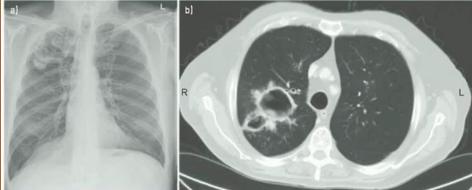

慢性空洞性肺曲霉病(CCPA):最常见,单发或多发的肺空洞(薄壁或厚壁),空洞内可包含一个或多个曲菌球或不规则的腔内物质,具有曲霉菌血清学和微生物学依据,并有明显肺部和全身症状,至少3个多月的观察有放射影像学进展(新发空洞,空洞外周浸润增加及纤维增生增加)。

1、胸部影像学(CT最佳)符合CPA表现;